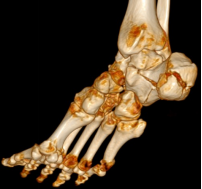

回到前文所述的患者程某,其X线片及CT检查提示其骨折系波及关节面的严重粉碎性骨折,具有明确的手术指征。